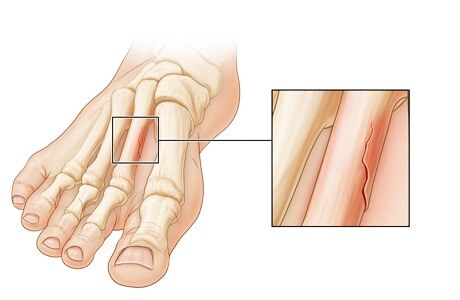

Брахидактилия

Это врождённая аномалия развития, характеризующаяся укорочением пальцев кистей и/или стоп из-за недоразвития или отсутствия фаланг.

На Р-граммах правой кисти в 2х проекциях: травматических, деструктивных изменений не выявлено. Структура костной ткани не изменена. Средняя фаланга пятого пальца укорочена, утолщена. По остальным отделам кисти-без явной костной патологии.

Заключение: Врожденная аномалия развития правой кисти- брахидактилия (брахифалангия) средней фаланги пятого пальца правой кисти.

Категория годности с данным диагнозом по ст.67(Отсутствие, деформации, дефекты кисти и пальцев), г) при наличии объективных данных без нарушения функций-Б3(годен к в/сл с незначительными ограничениями).